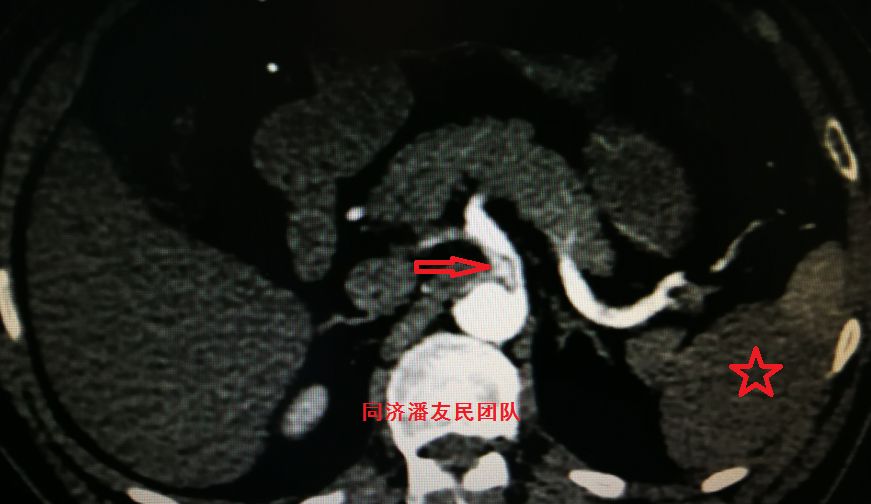

图10:CTA显示肠系膜上动脉由假腔供血(红箭头所示),真腔压闭,左肾及脾脏梗死(红星形所示)

图11:CTA显示双肾动脉由假腔供血(红箭头所示),左肾梗死(红星形所示)